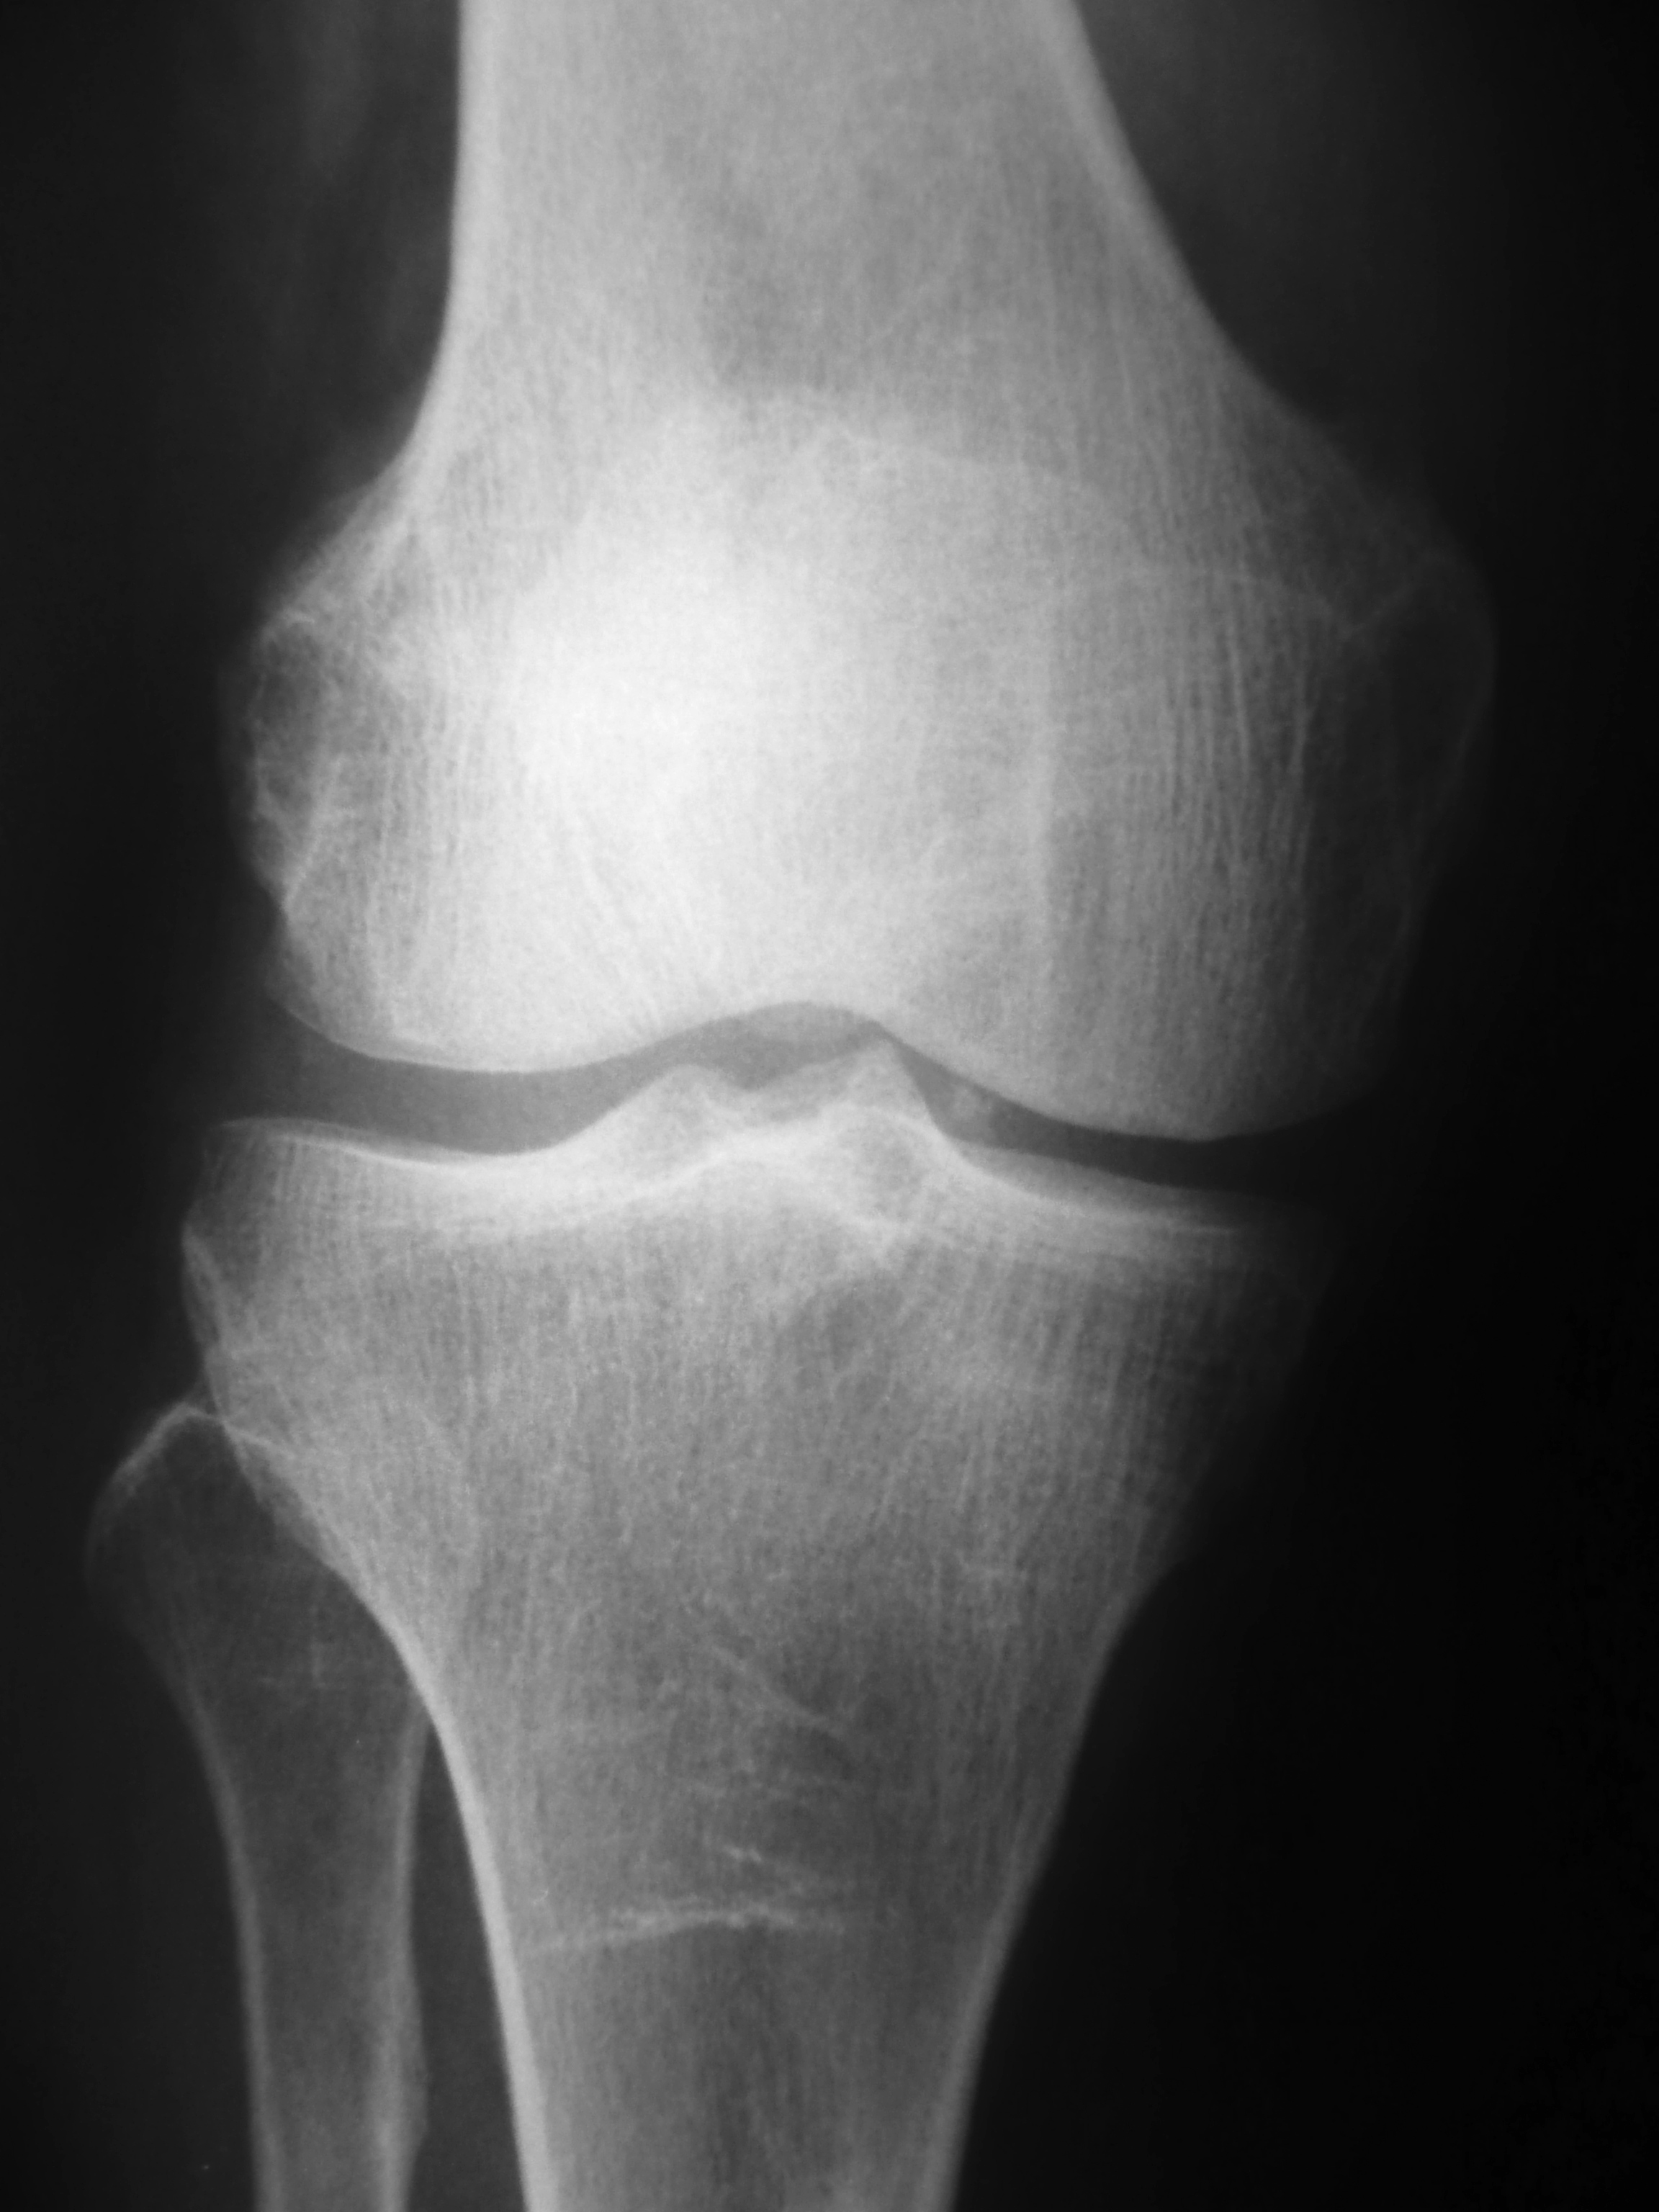

단순 방사선 촬영은 방사선학 초기 50년 동안 유일하게 사용 가능한 영상 기법이었다. 접근성, 속도, 저렴한 비용으로 인해 방사선 촬영은 방사선 진단에서 종종 1차 검사로 선택된다. CT 스캔, MR 스캔 및 기타 디지털 기반 영상에서 많은 양의 데이터를 얻을 수 있지만, 단순 방사선 사진으로 고전적인 진단을 얻을 수 있는 많은 질병(예: 다양한 유형의 관절염 및 폐렴, 골종양(특히 양성 골종양), 골절, 선천성 골격 이상, 특정 신장 결석 등)이 있다.

단순 방사선 촬영은 방사선학의 초기 50년 동안 유일하게 사용 가능한 영상 기법이었다. 다른 기법에 비해 접근성, 속도, 저렴한 비용으로 인해 방사선 촬영은 방사선 진단에서 종종 1차 검사로 선택된다. 또한 CT 스캔, MR 스캔 및 기타 디지털 기반 영상에서 많은 양의 데이터를 얻을 수 있지만, 단순 방사선 사진으로 고전적인 진단을 얻을 수 있는 많은 질병이 있다. 예를 들어 다양한 유형의 관절염 및 폐렴, 골종양(특히 양성 골종양), 골절, 선천성 골격 이상, 특정 신장 결석 등이 있다.